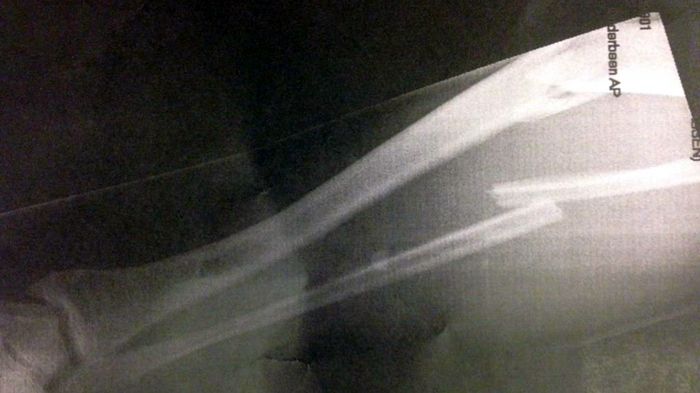

Μεγάλος άτυχος του Assen ο πιλότος της Pata Honda, Leon Haslam που έσπασε το καλάμι του στα δοκιμαστικά!

Ο Haslam έσπασε και τα 2 κόκκαλα στο καλάμι, και υπεβλήθη σε επέμβαση για να τοποθετηθεί λάμα στο πόδι του.

Ο Sykes είναι γνωστός για τις απίστευτες ικανότητες του στο βρεγμένο, και στα δοκιμαστικά του Assen που έγιναν με πολύ κακές καιρικές συνθήκες, κανείς δεν μπόρεσε να τον πλησιάσει. Ο Βρετανός αναβάτης σημείωσε χρόνο 1.57.190, με το δεύτερο Sylvain Guintoli να βρίσκεται 1.634 δευτερόλεπτα πίσω του! Ο κακός καιρός οδήγησε σε πτώσεις, τόσο τον Giugliano, όσο και τον Badovini, όμως τα χειρότερα ήρθαν για τον Leon Haslam της Pata Honda, που έπεσε άγαρμπα, με τον τροχό να του πιάνει το πόδι και να το σπάει! Έτσι, ο 29χρονος Βρετανός βρέθηκε και με τα δύο κόκαλα στο καλάμι του αριστερού του ποδιού σπασμένα και οδηγήθηκε άμεσα στο νοσοκομείο.

Βγήκε κόκκινη σημαία, και τα δοκιμαστικά διακόπηκαν άδοξα. Όταν ο αναβάτης της Pata Honda μεταφέρθηκε στο τοπικό νοσοκομείο, εκεί δυστυχώς επιβεβαιώθηκε το κάταγμα τόσο στην κνήμη, όσο και στην περόνη. Στη συνέχεια ο Haslam μεταφέρθηκε στο νοσοκομείο του Gronigen, όπου και υποβλήθηκε σε εγχείρηση για να τοποθετηθούν λάμες στο πόδι του. Περαστικά στον Leon, και του ευχόμαστε να επιστρέψει σύντομα στις πίστες.